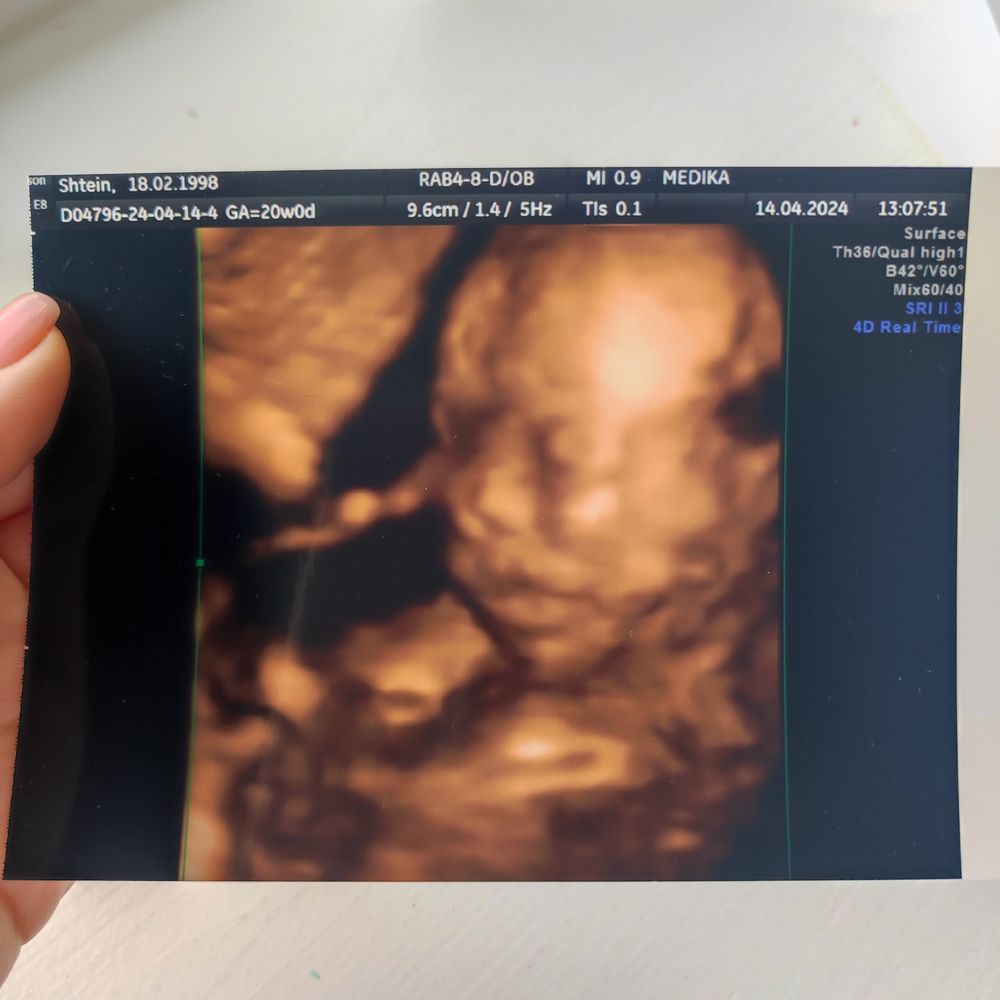

Лилия 2 года ура, внутри меня растет дочь всё о Еве какое счастье сходить на скрининг и узнать, что с тобой и с малышкой все хорошо ☺️ ждём тебя к сентябрю, моя девочка ❤️ Посмотрите еще 20 записей на эту тему Отменить Ответить первые шевеления малышки Еве один месяц Чаты Беременных Выберите чат: Январята-2026 Февралята-2026 Мартята-2026 Апрелята-2026 Майчата-2026 Июнята-2026 Июлята-2026 Августята-2026